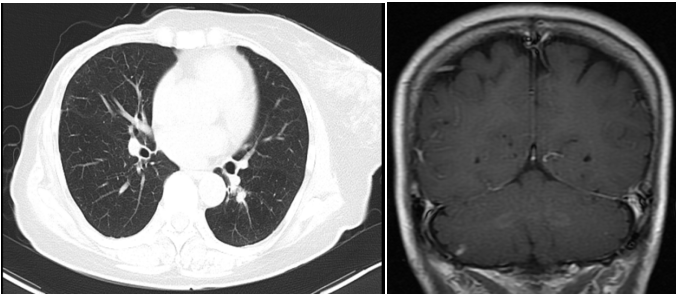

图2. 2019.01两肺转移灶

两个疗程后复查CT:右乳Ca伴右腋下淋巴结M(较前相仿),伴两肺弥漫性转移(图3,较前缓解),肝脏转移灶消失(图3)。胸腰椎转移灶,较前相仿。疗效评价PR。

图3. 2019.03两肺转移灶(左图),肝左叶转移灶(右图)